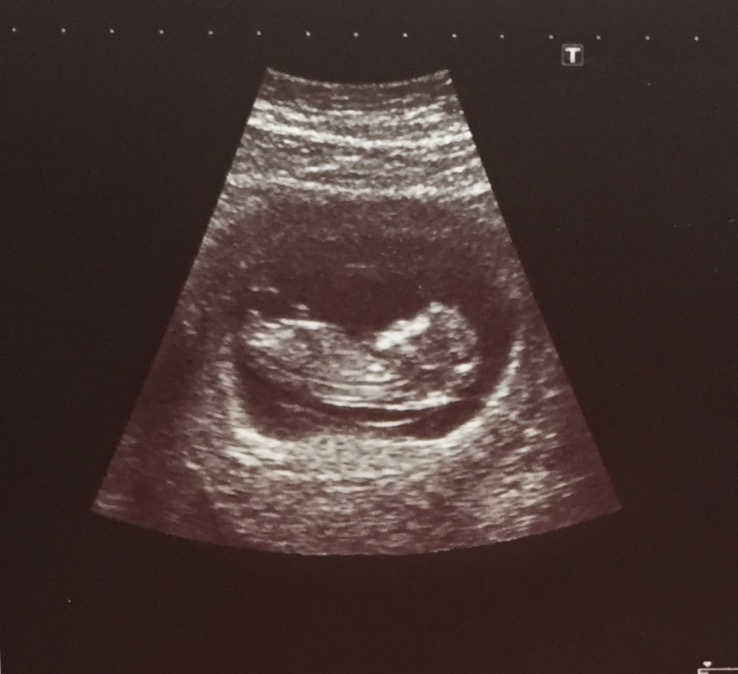

Hi I'm new to gender dreaming and have been obsessed with looking at my babies nub as soon as I heard about..... Could any of you loverly ladies help me and have a look at my babies nub I was on a different site and got mixed boy and girls?? I really don't know what to think??? thank you so much in advance 12w +6days Attachment 32397Attachment 32398